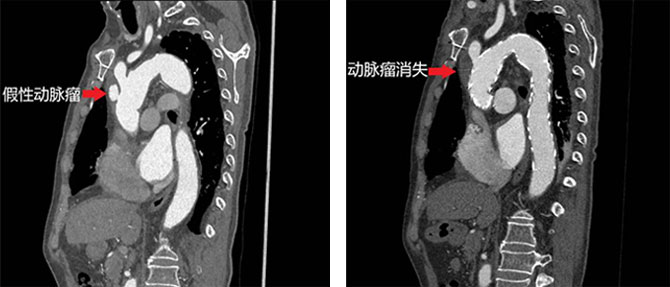

病例三:不开胸治疗高龄升主动脉假性动脉瘤患者

第三例患者为76岁男性,患有“主动脉瓣关闭不全和主动脉窦动脉瘤”,曾接受过复杂的主动脉瓣生物瓣置换术和主动脉根部置换术。近期复查发现升主动脉远段存在假性动脉瘤,随时可能破裂。按照传统治疗方案,患者需要接受再次正中开胸,在体外循环心脏停跳下行升主动脉置换+全主动脉弓置换。

考虑到患者高龄,接受该类手术的风险极高。李欣和杨珏医生在详细分析患者病情和主动脉解剖特点后,决定为患者植入由心脏大血管外科参与研发的A型主动脉综合征全腔内重建系统。该系统可以微创治疗A型主动脉夹层、升主动脉假性动脉瘤和升主动脉溃疡等多种主动脉疾病。

经过充分的术前准备工作和严谨的临床试验入组工作后,李欣和杨珏医生仅通过颈部两处4cm长的微创切口,利用A型主动脉综合征全腔内重建系统,在非开胸非体外循环下成功为患者实施了左锁骨下动脉到右颈动脉旁路移植术和胸主动脉夹层腔内隔绝术。手术过程顺利,患者术后当晚拔除气管插管,术后第1天便顺利转回普通病房,术后第3天顺利出院。此项微创技术不仅为患者提供了安全有效的治疗,还减少了传统手术的创伤,显著缩短了恢复时间。

术前(左侧)和术后(右侧)CT